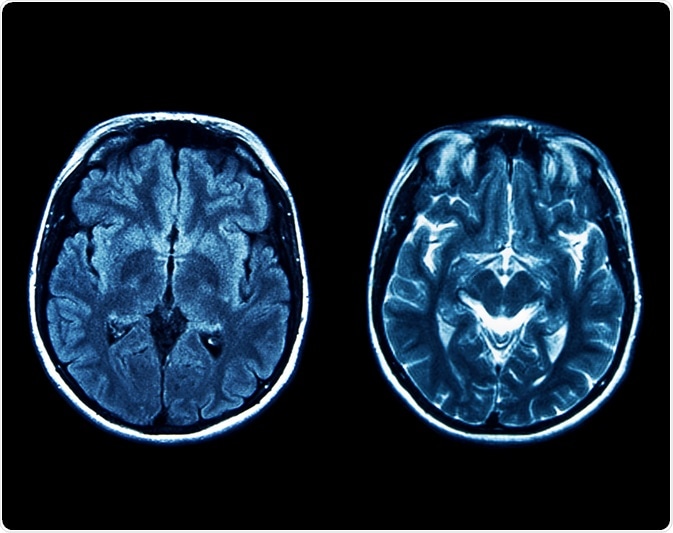

Joubert syndrome is an autosomal recessive neurodevelopmental disorder that is characterized by a brain abnormality called the “molar tooth sign.” The molar tooth sign, which is visible on brain imaging studies like magnetic resonance imaging (MRI), results from the abnormal development of regions in the cerebellar vermis and the brainstem. These specific brain abnormalities resemble the cross-section of a molar tooth when seen on an MRI, hence the name.

Image Credit: gmstockstudio / Shutterstock.com